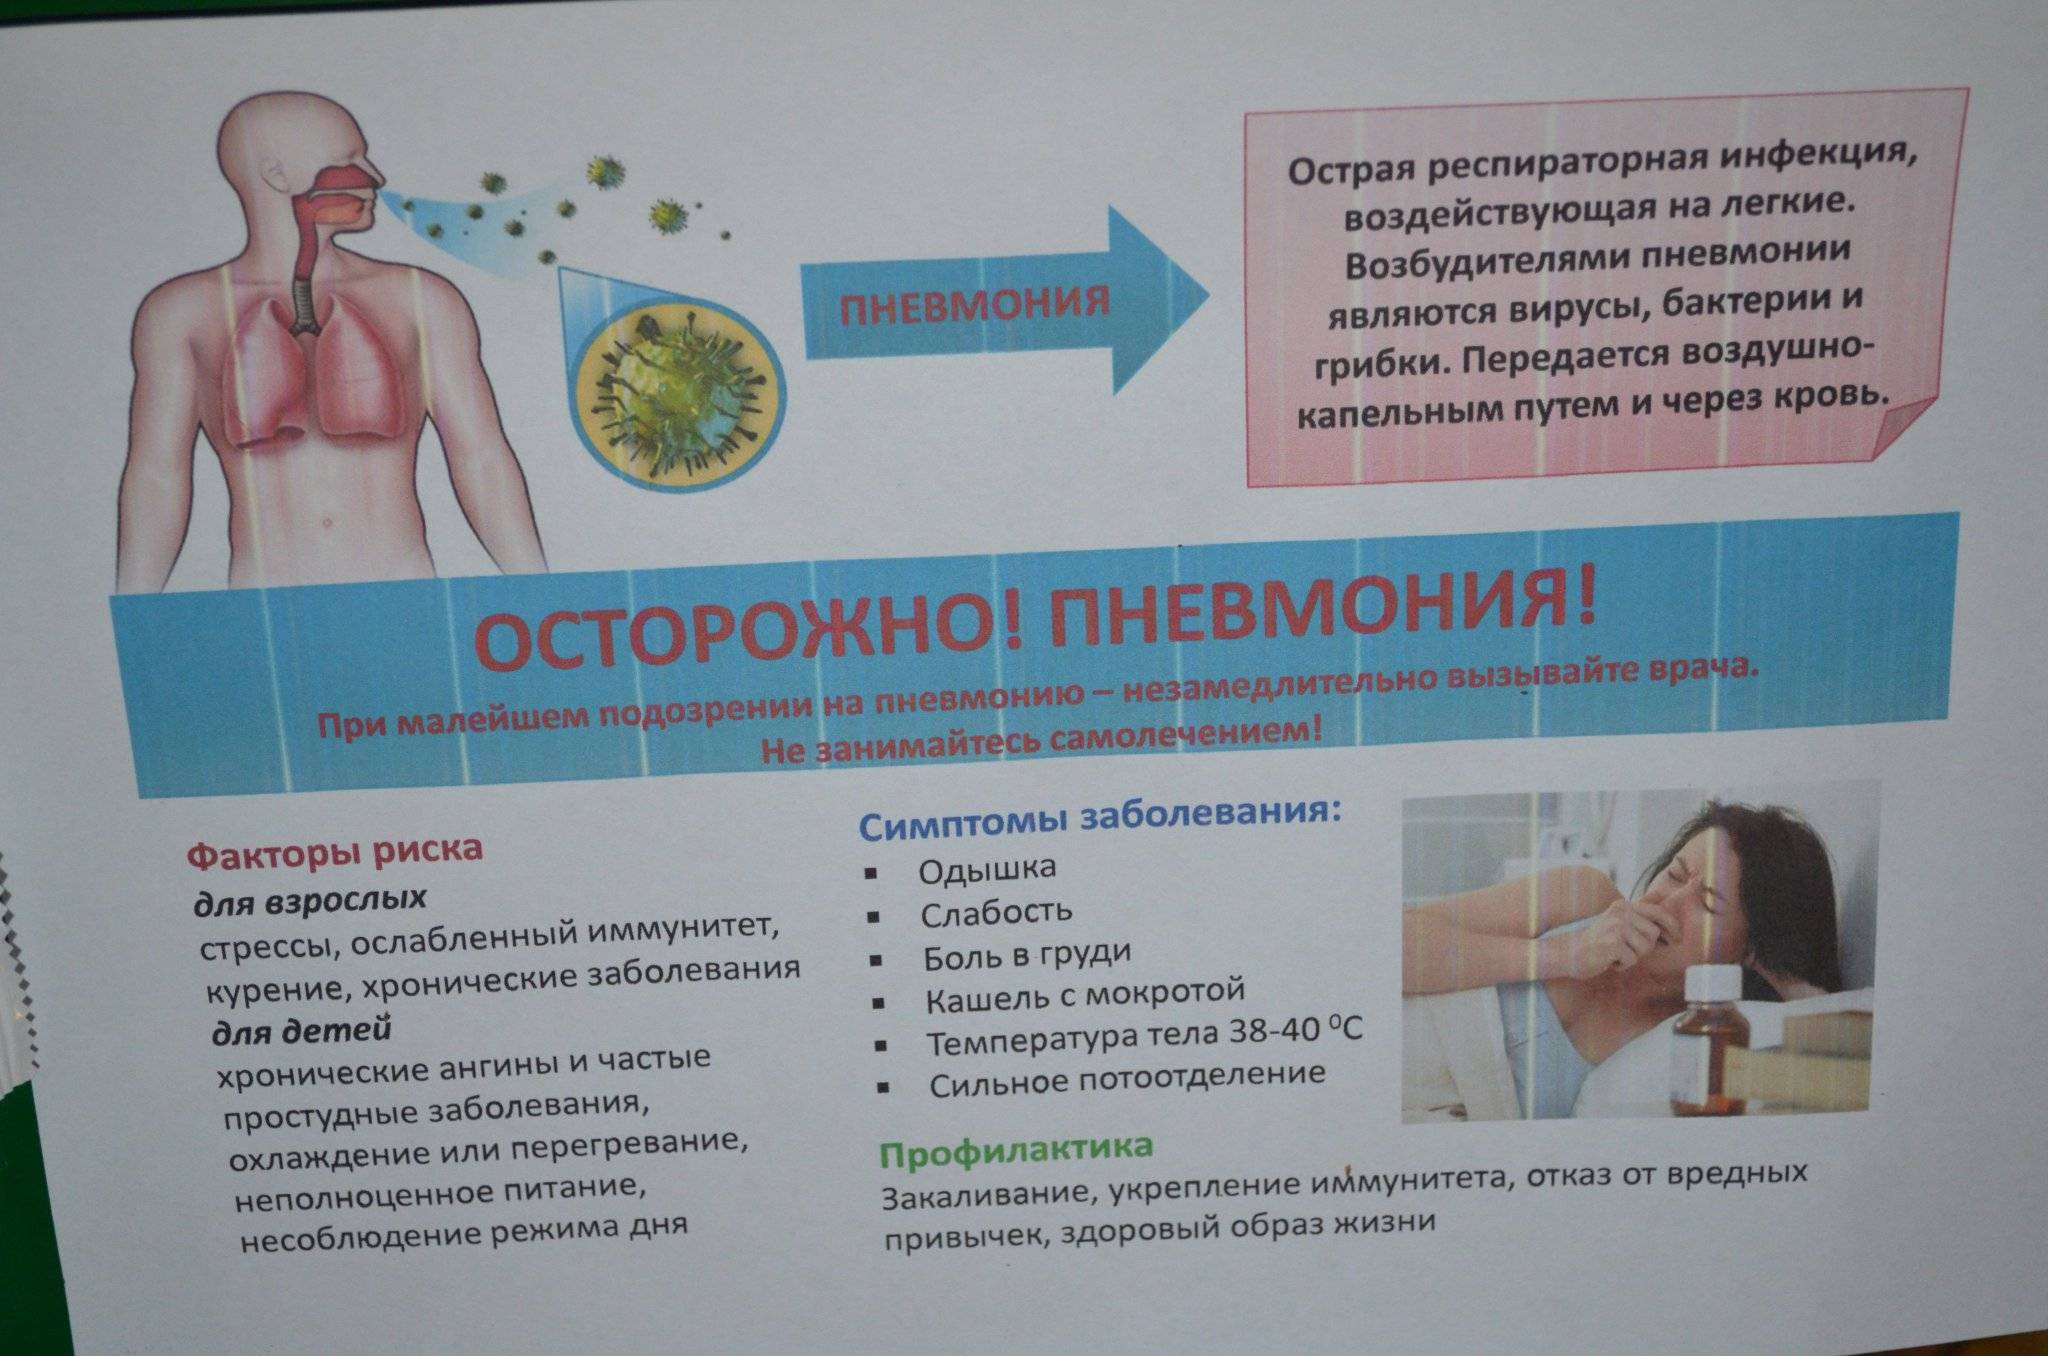

Фотографии бактерий, вызывающих бактериальные пневмонии у животных

Раздел: Другие животные